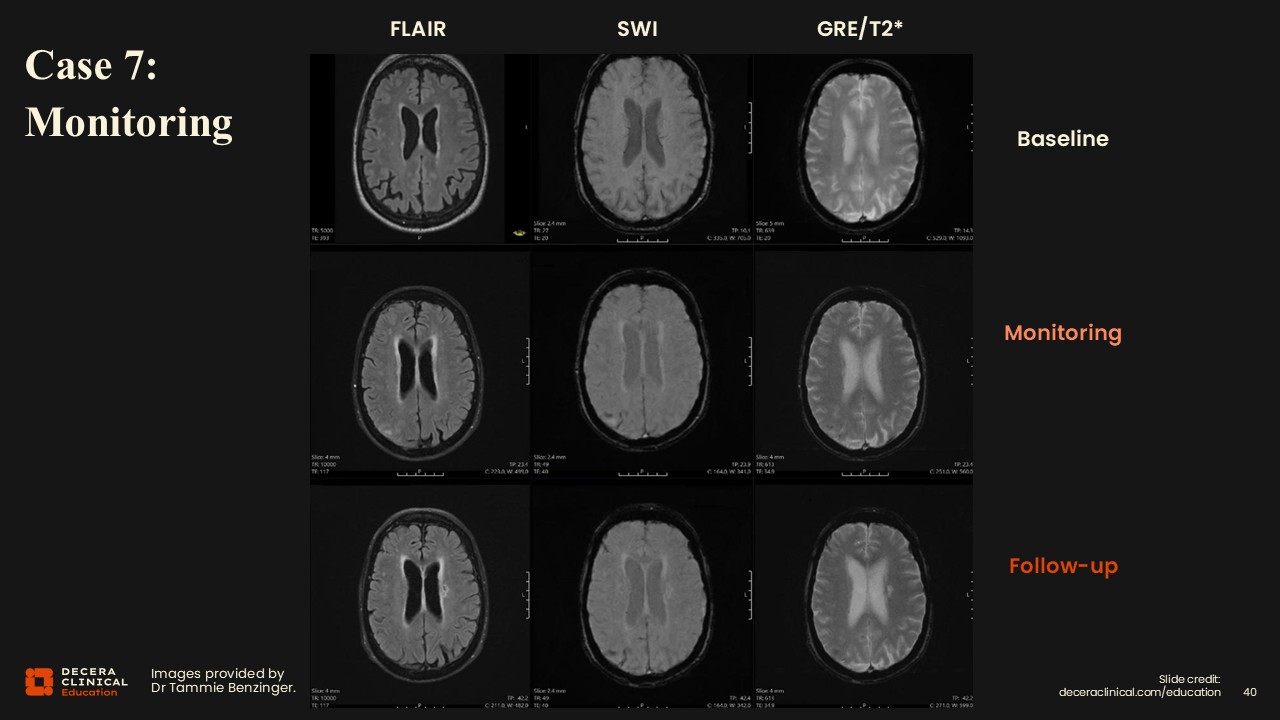

Case 7: ARIA Detection on Monitoring

Dr Benzinger:

For the final case, we have the same 3-visit setup: baseline, monitoring, and follow-up for a patient receiving ATT.

Case 7: ARIA Detection on Monitoring (Detail)

Upon inspection, vasogenic edema and sulcal effusions are noted on FLAIR, and then findings on SWI, and very subtle on the GRE/T2* as well.

Case 7: ARIA Detection on Monitoring (Grading)

Findings are consistent with mild ARIA-E and moderate ARIA-H with 2 siderosis.